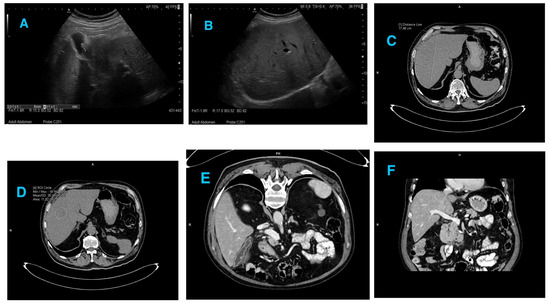

The abdominal ultrasound and CT scan showed hepatic steatosis and a polyp of the gallbladder (Appendix A, Figure A1A–F). Due to uncertainty in determining the reason for liver failure, a biopsy was performed, which revealed lymphoplasmacytic interface hepatitis (Appendix B, Figure A2a–g). During the hospitalization, steroid therapy with prendisolone was administered. Over the next few days an improvement in clinical status was observed, including the reduction of the jaundice and normalization of the liver enzymes.

Figure A1. Pictures (AF) Diagnostic imaging. (A) A polyp in the gallbladder shown in the ultrasound examination of the abdomen. (B) Hepatic steatosis of the liver shown in the ultrasound examination of the abdomen. (C) Enlarged liver shown in the abdominal CT scan with contrast. (D) Hepatic steatosis shown in the abdominal CT scan with contrast. (E) A polyp in the gallbladder shown in the abdominal CT scan with contrast. (F) Homogeneous intraluminal signal of the lumen of the portal vein shown in the abdominal CT scan with contrast.